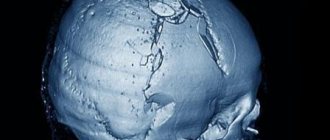

Перелом свода черепа возникает после сильных ударов с вдавлением и разрывом костей черепа. Он характеризуется:

• наличием деформации, вдавления или выступов,

• подвижностью костных отломков и крепитацией (звук, напоминающий такой при ходьбе по снегу в мороз).

• при открытом переломе в ране можно увидеть вещество головного мозга.